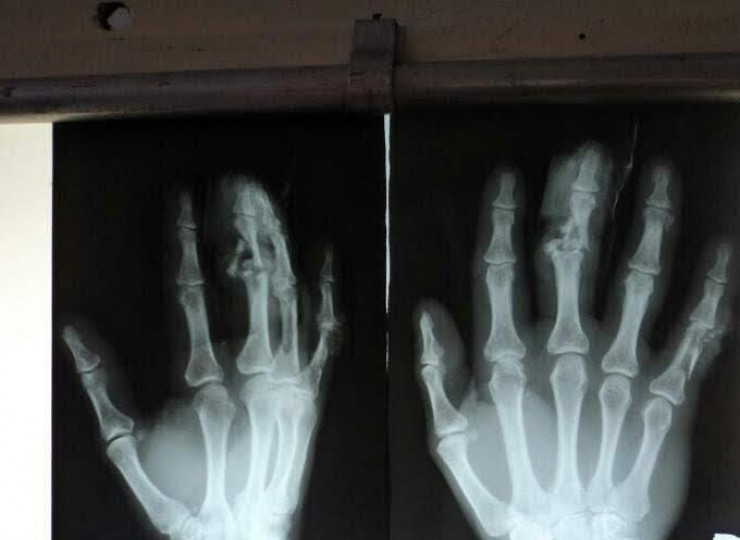

Причина - травма. Хардон сломал руку во время спарринга. Врачи запретили ему драться.